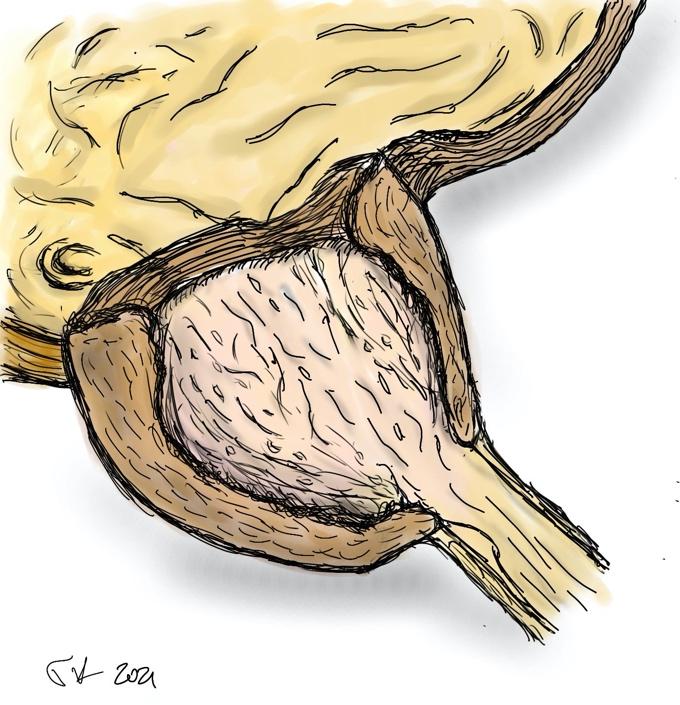

- το προστατικό αδένωμα αποκολλάται από την κάψα με τη βοήθεια του ειδικού ηλεκτροδίου εκπυρήνισης (εικόνες 1-4)

- το αδένωμα έχει πλέον αποκολληθεί από την προστατική κάψα και προωθείται στην ουροδόχο κύστη (εικόνες 5-6)

Εικόνες 1-4

εικόνες 5-6